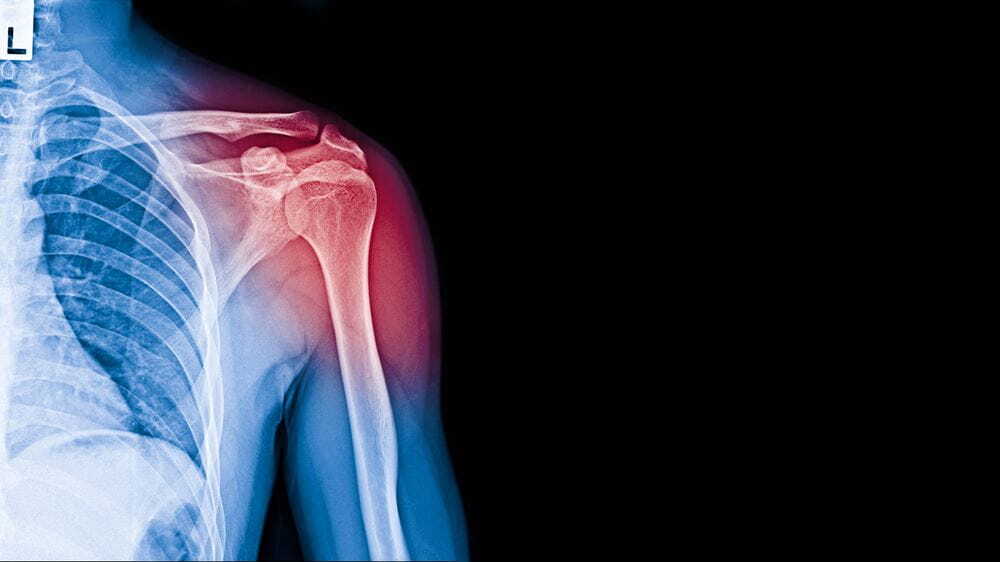

어깨뼈 골절 수술 후, 본격적인 물리치료 및 재활치료가 시작됩니다. 이때까지 깁스 등의 고정 상태가 유지되었지만, 이제부터는 근육과 관절을 복원하고 활동성을 회복하기 위한 치료가 중요합니다. 물리치료와 재활치료는 통증 경감 뿐만 아니라 움직임의 범위를 늘리고 근력을 향상시키는 데 도움을 줍니다.

물리치료와 재활치료는 개인의 상태와 의사의 지시에 따라 다양한 운동 및 치료 방법을 포함합니다. 이러한 치료는 수술 후 약 4주 정도부터 시작됩니다.

도수치료는 어깨뼈 골절 수술 후 복원 과정에서 중요한 부분입니다. 그러나 도수치료는 일반적으로 건강보험 적용 대상이 아니므로 비용이 발생합니다. 대략적으로 1회당 5만원 정도의 비용이 들 수 있습니다. 따라서 도수치료에 대한 비용은 병원 및 치료 기관에 따라 다를 수 있으며, 실비보험을 통해 청구할 수 있습니다.